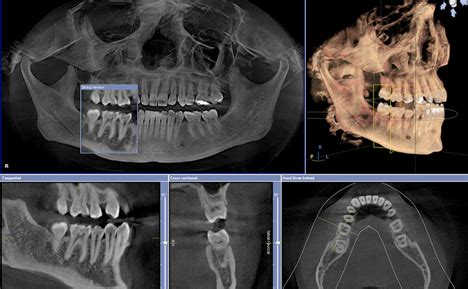

1. Panoramic X-Ray

2. CBCT 3D Imaging

CBCT Scan (3D Xray)

• Reveals extra canals 2D x-rays miss

• Detects deep cracks or infections

• Like lifting the hood for complete engine view vs quick glance

We take CBCT 3-D images which are different than your general dentist provides.